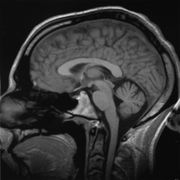

Brain

"It is well established that men have a larger cerebrum than women by about 8–10% (Filipek et al., 1994; Nopoulos et al., 2000; Passe et al., 1997a,b; Rabinowicz et al., 1999; Witelson et al., 1995)." However, what is functionally relevant are differences in composition and "wiring", some of these differences are very pronounced. Richard J. Haier and colleagues at the universities of New Mexico and California (Irvine) found, using brain mapping, that men have more than six times the amount of grey matter related to general intelligence than women, and women have nearly ten times the amount of white matter related to intelligence than men.

Gray matter is used for information processing, while white matter consists of the connections between processing centers. Other differences are measurable but less pronounced. Most of these differences are known to be produced by the activity of hormones, hence ultimately derived from the Y chromosome and sexual differentiation. However, differences arising from the activity of genes directly have also been observed.